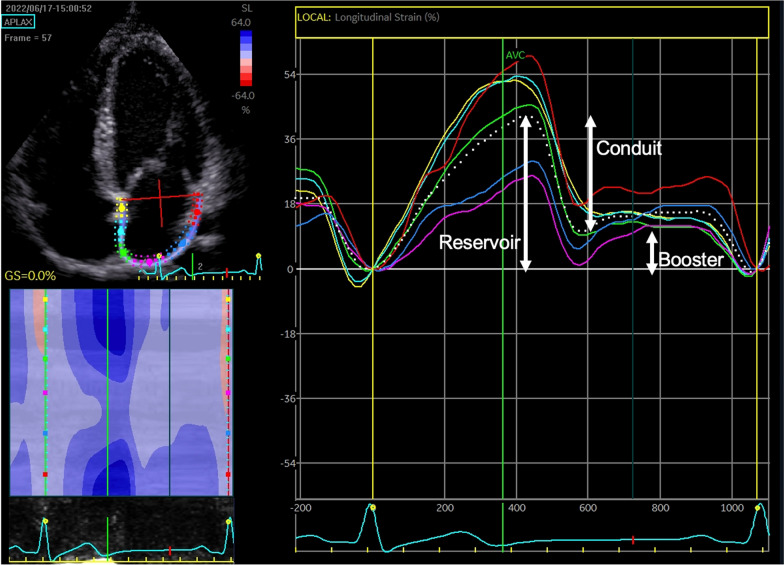

Offline analysis of strain was made in accordance with current guidelines [33]. A single cardiac cycle was used, and zero strain reference was set at ventricular end diastole. The region of interest (LA or RA myocardium) was traced and was divided into six equidistant segments which were then tracked, and global atrial strain for reservoir, conduit, and booster strain were calculated as an average of the six segments (see Fig. 1). Satisfactory tracking was determined by the software and validated by the operator. Left atrial stiffness index was calculated as the ratio of E/E’ to LA reservoir strain [20].

Fig. 1.

Measurement of left atrial reservoir, conduit and booster strain in the apical four chamber view